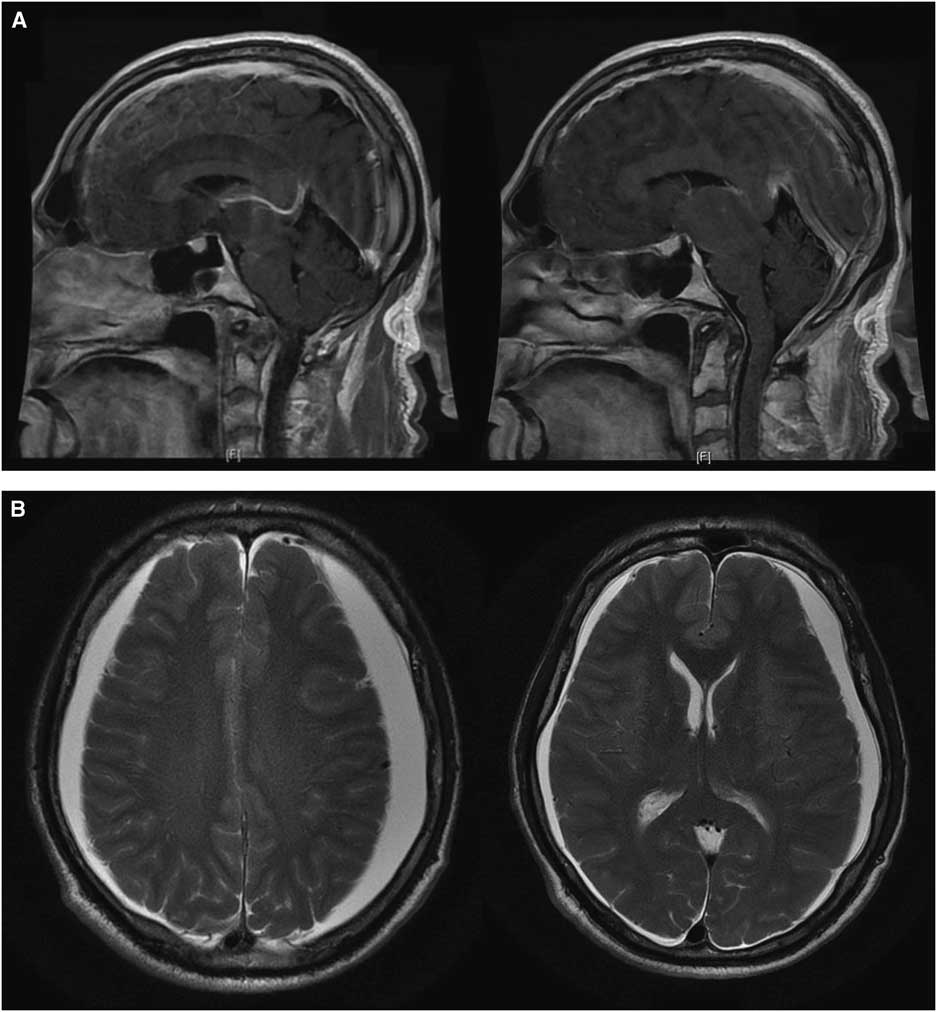

This 62-year-old right-handed gentleman presented in 2008 with facial chorea and was genetically proven to have HD. His symptoms remained stable for several years. He required no treatment. He was fully independent and working full time as a nuclear engineer. In 2016, he developed a progressive holocephalic orthostatic headache associated with marked fatigue, nausea and vomiting, and gait disturbance. After several months he developed worsening and more widespread chorea such that he was unable to work and required assistance with his activities of daily living. He also had progressive cognitive decline (5-point decrement on repeat MoCA 23/30). Brain MRI revealed findings suggestive of SIH with downward sagging of the brain, diffuse pachymeningeal enhancement (Figure 1A) and bilateral small subdural hygromas (SDHs) (Figure 1B). Spinal CT myelography identified a possible small CSF leak posteriorly at the C1-C2 level. This was treated twice with CT-guided epidural blood patch (EBP) with only temporary improvement. A week later he developed worsening chorea, disorientation and hallucinations. It was thought his clinical change was consistent with Huntington’s and he was started on zopiclone and risperidone.

Figure 1 (A) Initial T1 sagittal post-gadolinium brain MRI slices demonstrating radiologic findings of spontaneous intracranial hypotension including diffuse pachymeningeal enhancement, downward displacement of the brain with sagging of the brainstem, and effacement of suprasellar and prepontine cisterns. (B) Initial T2 axial brain MRI slices showing enlargement of subdural spaces with CSF signal compressing both cerebral hemispheres with minimal left-to-right midline shift.